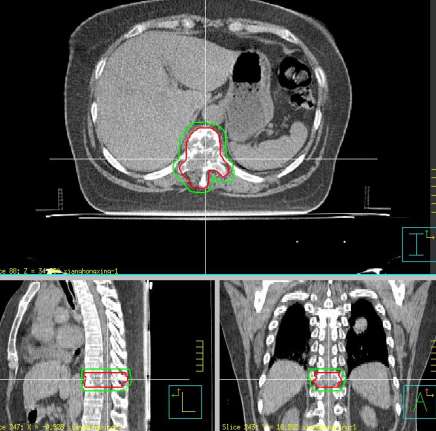

患者项xx,女,60岁,因咳嗽伴腰骶部疼痛2个月,加重1周入院。核磁:胸10椎体及附件转移继发椎管狭窄,脊髓受压;寰椎侧块膨大伴异常信号,不除外转移。临床诊断:左肺下叶腺癌(cT4N3M1,IV期),侵及降主动脉,双侧纵隔淋巴结转移,椎体转移,双肺炎,肝硬化-代偿期,高血压病3级(极高危险组),上消化道出血。患者骨痛剧烈,平车推入病房。2017年4月给予姑息减症放疗,靶区PTV1为胸10椎体及附件, 6MV-X线调强放疗,单次量8Gy,放疗组织剂量8Gy/1次/1天。放疗后疼痛缓解,现行动自如,靶向治疗中。